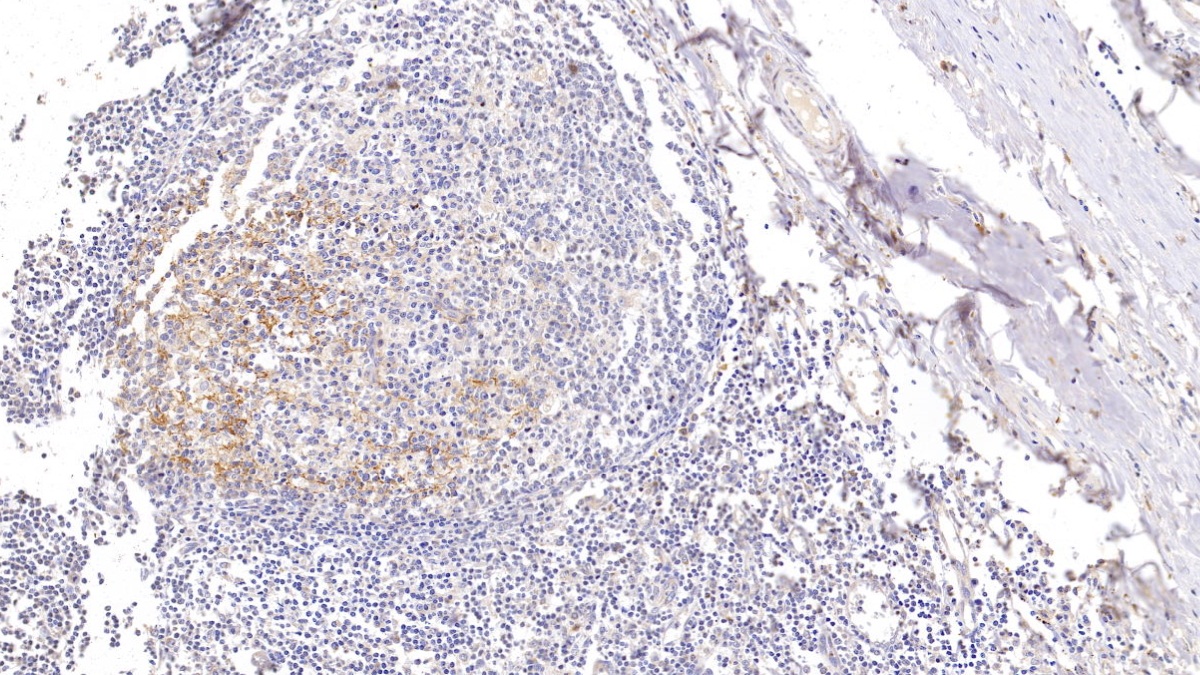

Polyclonal Antibody to Syndecan 4 (SDC4)

Product No.: PAB939Hu01

Organism species: Homo sapiens (Human)

Monoclonal Antibody to Syndecan 4 (SDC4)

Product No.: MAB939Hu22

Organism species: Homo sapiens (Human)